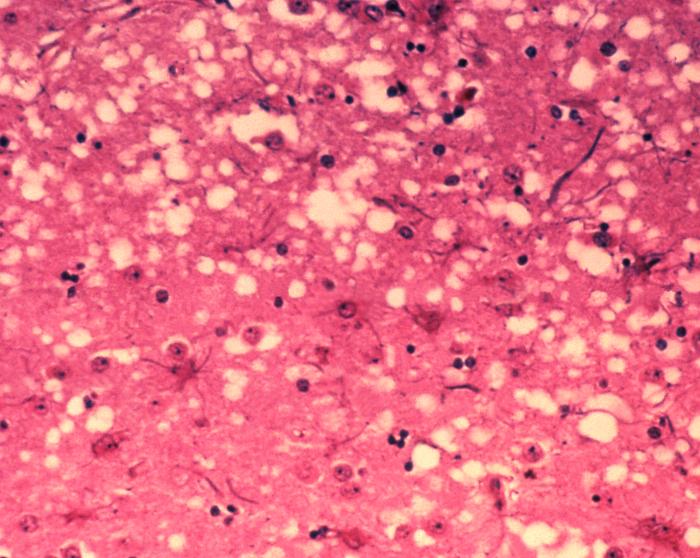

Due uomini e una donna sarebbero morti a Grosseto per la malattia di Creutzfeldt-Jakob (MCJ), una grave patologia degenerativa che colpisce il cervello, spesso associata al morbo della mucca pazza di cui è la variante umana.

Assistiti dagli avvocati Alessandro e Roberto Cerboni, i familiari del sessantenne hanno ottenuto una prima risposta dall’autopsia: la forma di encefalopatia spongiforme che ha ucciso il sessantenne sarebbe quella sporadica, la forma più comune, che colpisce circa 1 persona su un milione ogni anno nel mondo. Rappresenta circa l’85% dei casi e interessa solitamente individui di età superiore ai 40 anni, in genere intorno ai 65 anni. Per questa forma non esiste una causa nota.